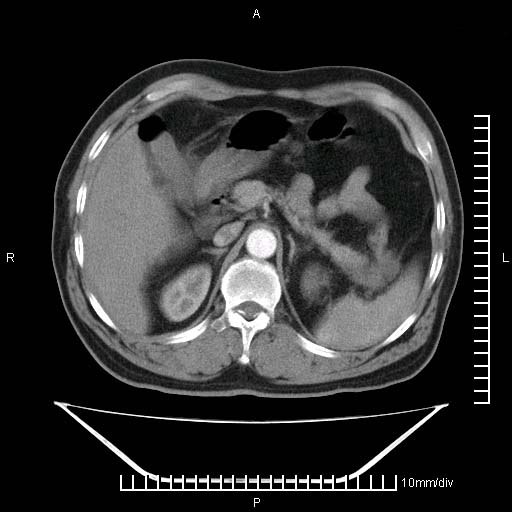

标题: CT25082:肝脏增强:男性,70岁 [打印本页]

标题: CT25082:肝脏增强:男性,70岁

患者以心脏疾病收住院,腹部无明显症状,b超查肝脏有占位。

肝内多发转移瘤,右下肺炎症并少量胸水。胃壁增厚建议胃镜,胰尾部“病变”为肠管。

1)肝脏多发性转移瘤(不排除胰尾癌转移所致可能)。2)腹水。3)右侧少量胸腔积液。

右下胸膜肥厚。

胰尾占位?结肠脾曲?

ct25082 结果:转移瘤

外院mr结果:胰尾恶性占位。

肝多发低密度灶;轻度强化,较水密度高,考虑转移,不排除肝脓肿